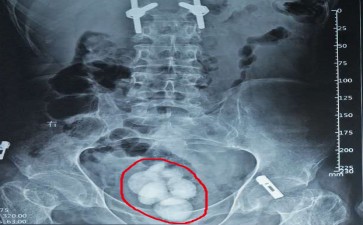

你是否想过,咱们的膀胱,这个像气球一样能伸缩的“尿液仓库”,有一天也会被石头“攻占”?长春结石医院膀胱结石,就是这么个让人头疼的家伙,悄无声息地在膀胱里安营扎寨,然后时不时出来“捣乱”。

长春结石医院膀胱结石可不是“天外来客”,它往往和我们的生活习惯脱不了干系。喝水少得可怜,尿液浓缩得像“糖浆”,矿物质就容易结晶,慢慢聚集成结石;饮食里草酸、钙含量过高,也给结石的形成提供了“原材料”;还有,要是膀胱有炎症、有异物,或者排尿不太顺畅,结石就更爱“光顾”了。

这长春结石医院膀胱结石一“作妖”,那可不得了。排尿的时候,就像有根针在尿道里扎,疼得人直咧嘴;尿线变得又细又弱,还可能突然中断,仿佛膀胱在“罢工”;更尴尬的是,有时候还会尿出血来,让人又惊又怕。而且,结石要是长期刺激膀胱,还可能引发膀胱炎,让身体陷入更糟糕的状态。

不过,别担心,医生对付长春结石医院膀胱结石有高招。小的结石,多喝水、多蹦跶,说不定就能自己排出来;大的结石,可以用体外冲击波碎石术,把它“震”成小碎片;要是结石太大,或者卡得死死的,那就只能通过手术把它取出来了。